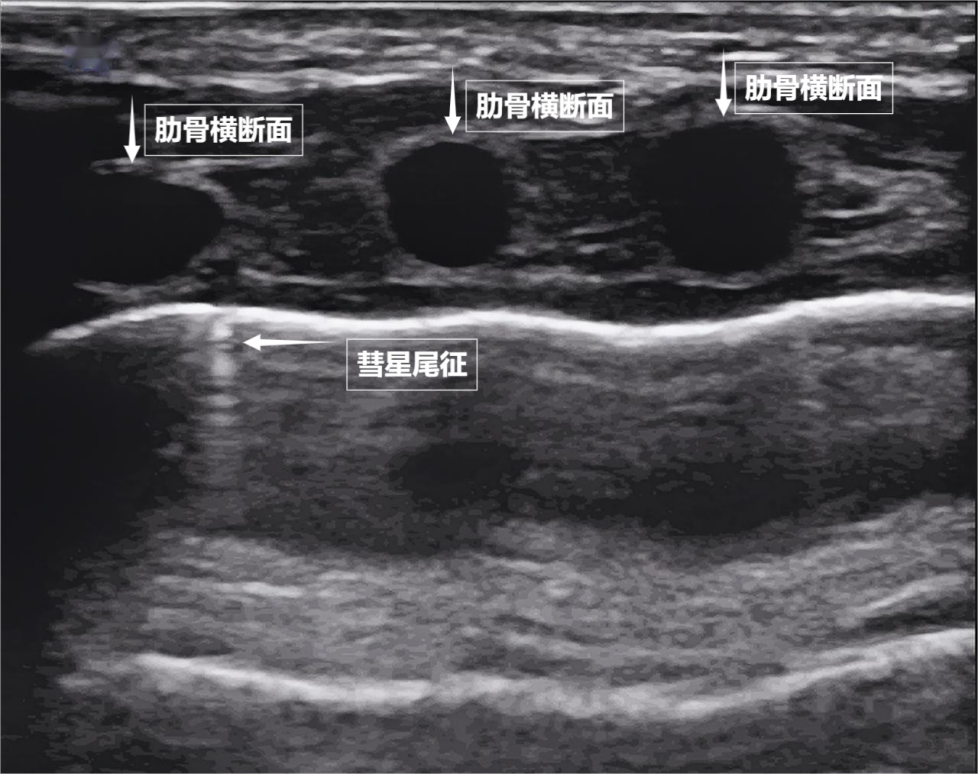

如果我們把超聲圖像調(diào)成實時動態(tài)模式,把“照片”變成“電影”,更神奇的一幕出現(xiàn)了。隨著呼吸,胸膜線會隨胸廓運動輕柔滑動,這就是“肺滑動征”。它意味著肺與胸壁正緊密相依、自由順暢地呼吸。若肺與胸壁間有氣胸或胸腔積液,這種滑動會消失。有時,在胸膜線下方還會出現(xiàn)細小的亮白色閃爍點,稱為“彗星尾征”(見下圖)。其少量、孤立出現(xiàn)時,通常是正常肺小葉間隔的反射,無需擔心。

圖為正常新生兒肺部超聲表現(xiàn)